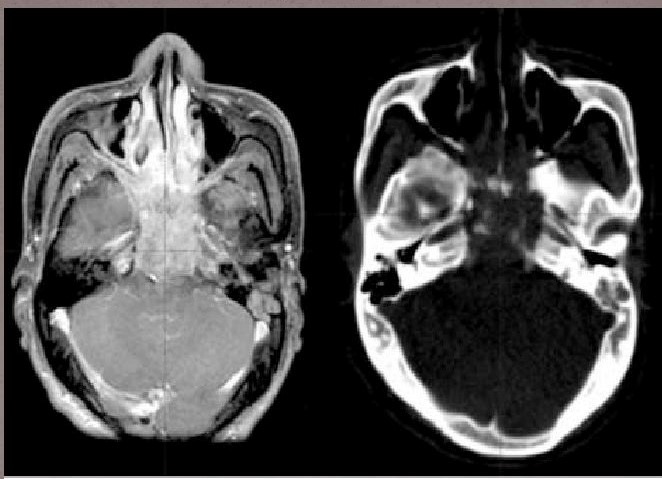

- КТ или МРТ. Томография показывает точную локализацию опухоли и ее распространение. Снимки визуализируют поражение межмышечной клетчатки нервов, разрушение костей основания черепа. Только по результатам магнитно-резонансной томографии удается выявить двустороннюю локализацию опухоли, в то время как другие методы исследования показывают наличие только на одной стороне лимфатических узлов. На поздних стадиях МРТ показывает прорастание опухоли в костные структуры, заглоточные лимфатические узлы и вещество головного мозга.